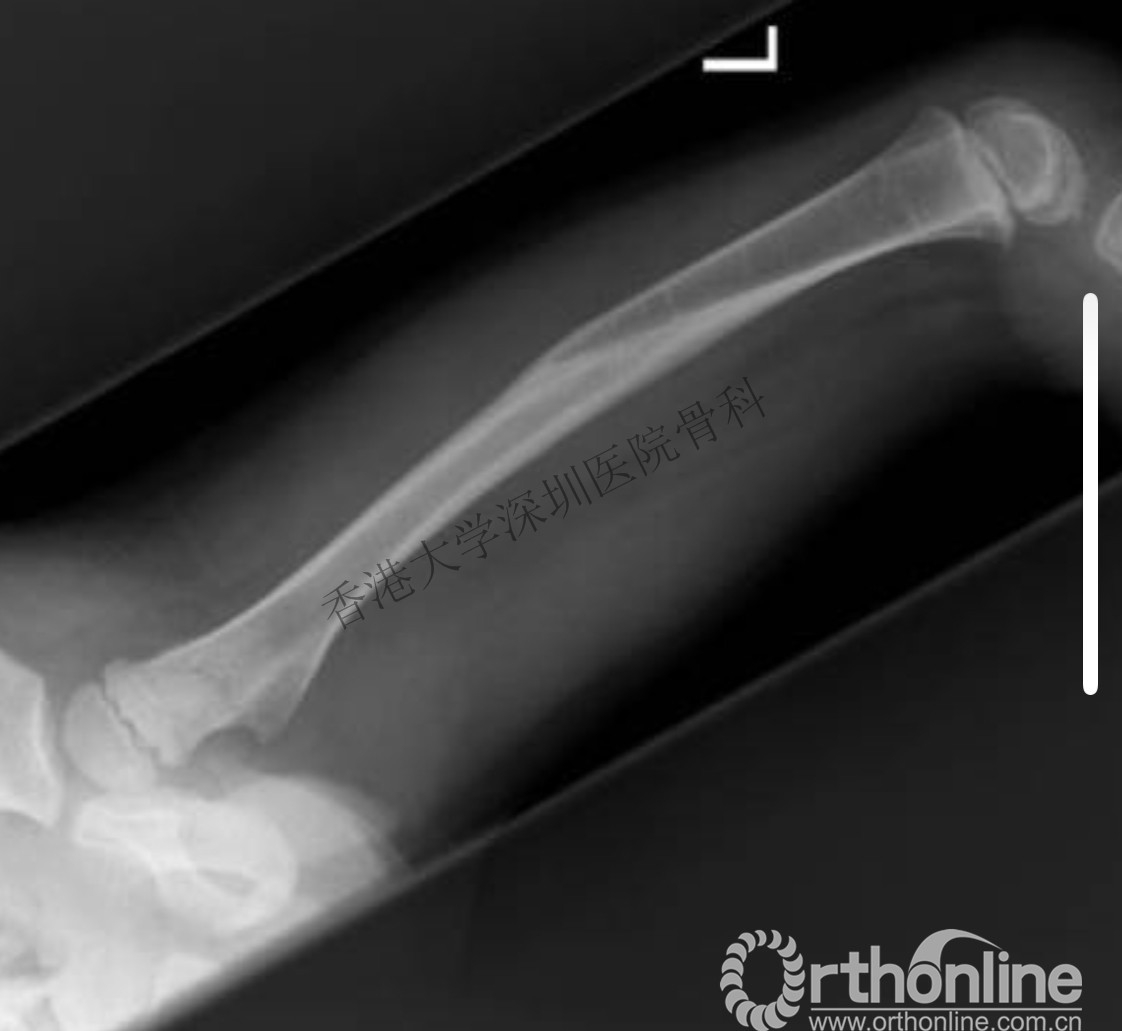

2岁儿童骨折,受伤时和1年后对比,塑型良好(受伤时)

2岁儿童骨折,受伤时和1年后对比,塑型良好(受伤1年后)

同时,我们也应该注意避免过度治疗,因为儿童骨骼具有良好的塑形能力,有时候并不需要解剖复位,很多对于成人无法接受的骨折移位,也可以得到良好的愈合和重塑。